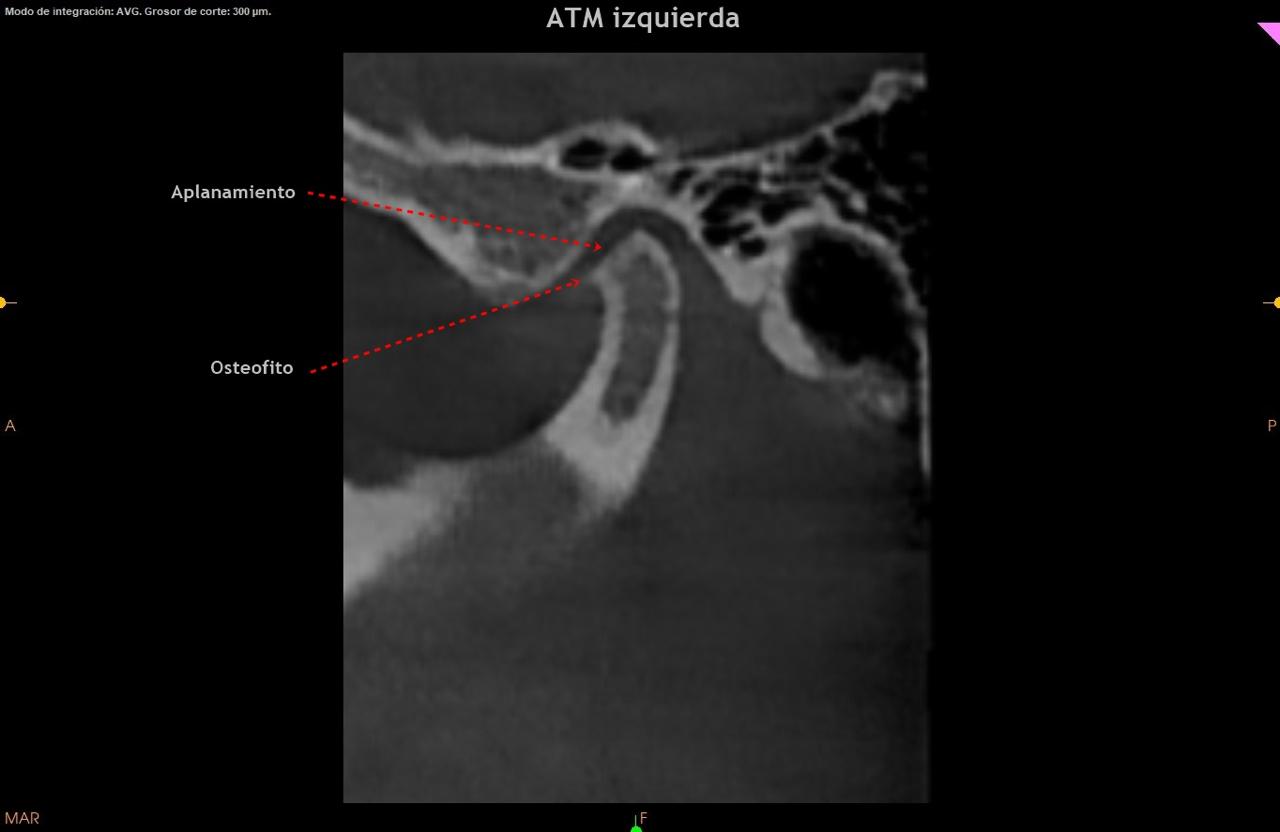

Los osteofitos en la ATM generalmente se desarrollan debido a la degeneración del cartílago que puede acompañar condiciones como la osteoartritis o el desgaste crónico de la articulación.

Realizar una evaluación clínica completa y usar estudios de imagen (como rayos X, tomografía computarizada o resonancia magnética, para confirmar la presencia de osteofitos y evaluar su impacto en la articulación. -destacó la Dra. Mónica Souza Paz, quien está graduada de la UNAM y cuenta con un posgrado en ortodoncia y especialidad en dicho campo.

Determinar si los osteofitos están relacionados con osteoartritis, trauma previo o malos hábitos, como apretar y rechinar los dientes (bruxismo).